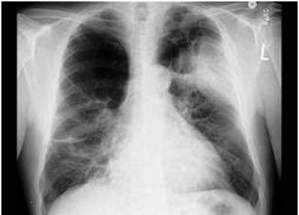

Rentgenološki znaci emfizema pluća su prilično nesigurni. To su:

- pojačana prozračnost pluća

- nisko položene baze

- prošireni interkostalni prostori

- povećani anteroposteriorni promeri pluća

Rentgenski snimak emfizema pluca

Rentgenski snimak emfizema pluća

Međutim, slični znaci se mogu naći i kod plućne hiperinflacije. Čini se da je za destruktivni emfizem pluća, zbog propadanja plućnog tkiva, specifičniji znak, smanjeni periferni vaskularni crtež pluća. Ipak, razumno je izraziti sumnju na sekundarni emfizem pluća, ako su izraženi mnogi klinički, radiološki ili funkcionalni znaci, pogotovo ako bolest traje duže vreme.